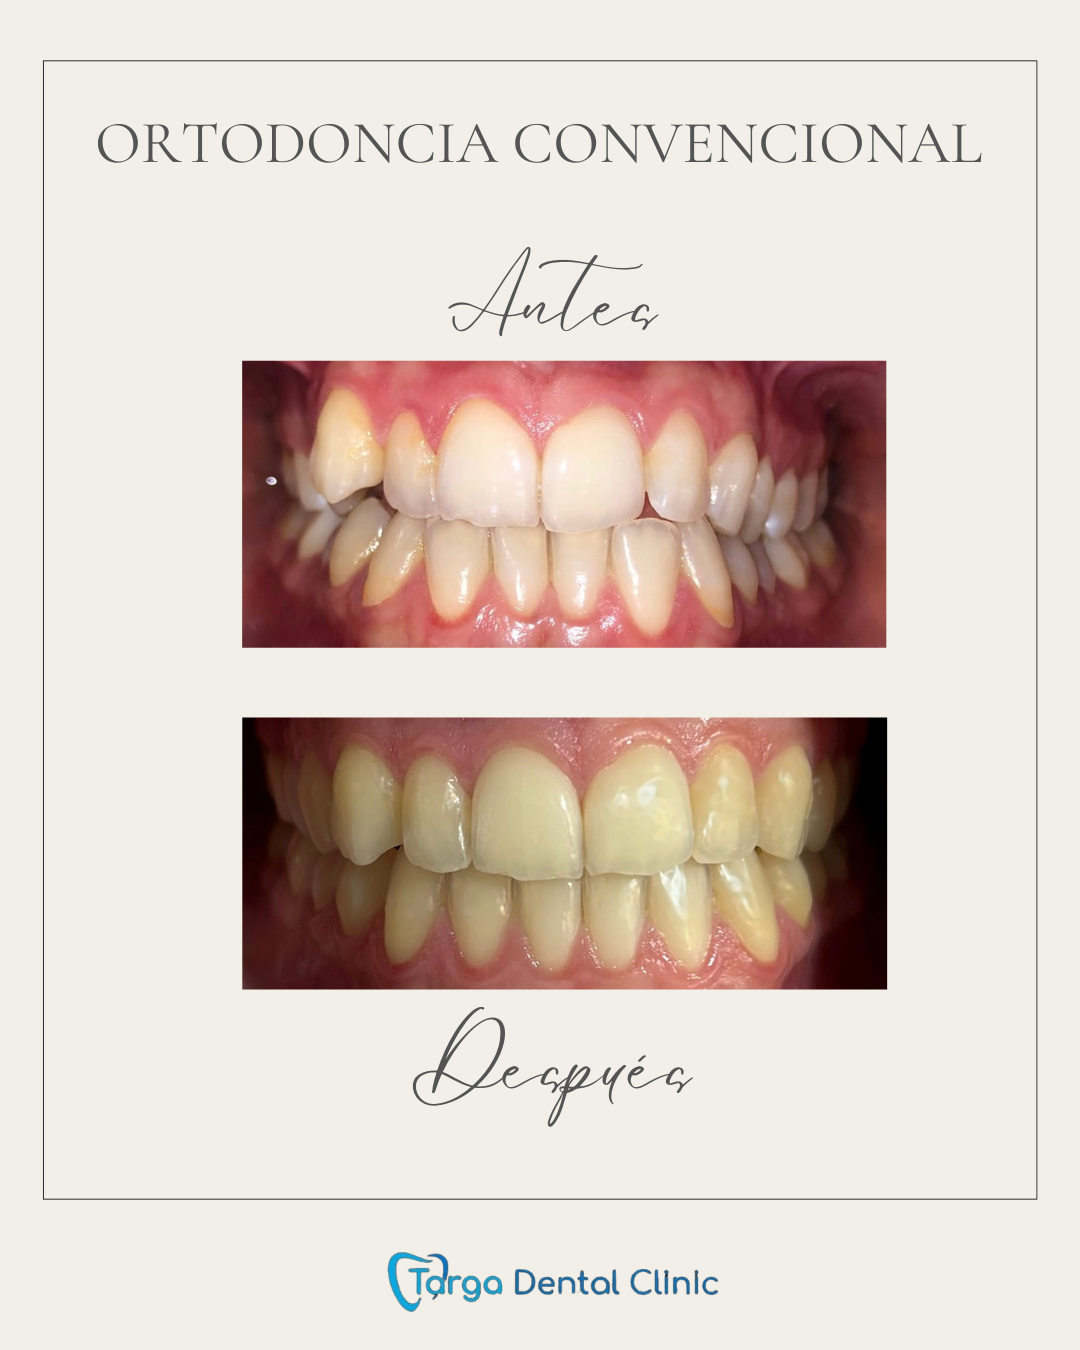

Ortodoncia y Odontopediatría

Ofrecemos tanto ortodoncia invisible con alineadores como ortodoncia fija con brackets.

Evaluamos cada caso y te recomendamos el más adecuado para ti. También ortodoncia para los más pequeños y los pacientes en crecimiento.

Tratamientos realizados en nuestra clínica